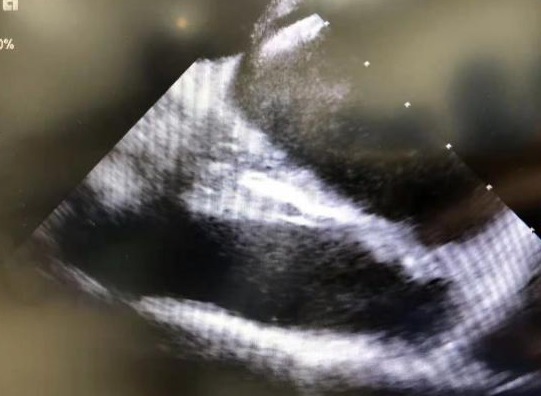

▲封堵盘展开

3月8日,手术如期进行。富丽娟为患者实施局部麻醉穿刺双侧股静脉,皮林带领团队运用心腔内超声(ICE),将只有三个多毫米直径的微小超声波探头,通过股静脉直接送到心脏内部,心房、卵圆窝、心耳等结构通过ICE成像实时清晰可见。包恩泽在ICE的直视和引导下,顺利将导管精准通过卵圆孔未闭处,释放封堵伞,完美封堵缺口,再次通过ICE观察和验证没有分流,手术圆满结束。本次手术在ICE实时监控下,从穿刺到手术成功历时不到30分钟。患者王女士于术后安返病房,并于术后第3天顺利出院。